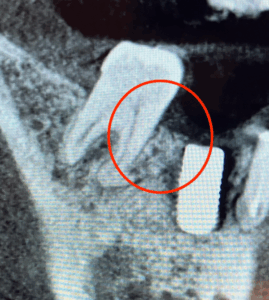

抜歯後、時間をおいてインプラントを埋入しました。抜歯時に骨の吸収が激しいところがあったため、インプラント埋入時に骨造成(自分の骨や人工骨などを使って骨を増やし、骨の土台を作る外科的な処置)も一緒に行いました。

画像がこちらになります。

1枚目の写真は抜歯後3〜4ヶ月後の骨の状態です。斜めに骨が無くなっているのがわかります。

2枚目の写真はインプラントを埋入して4ヶ月ほどたった時の画像です。インプラント脇の再生治療を行なった場所は、しっかり骨ができているのがわかります。